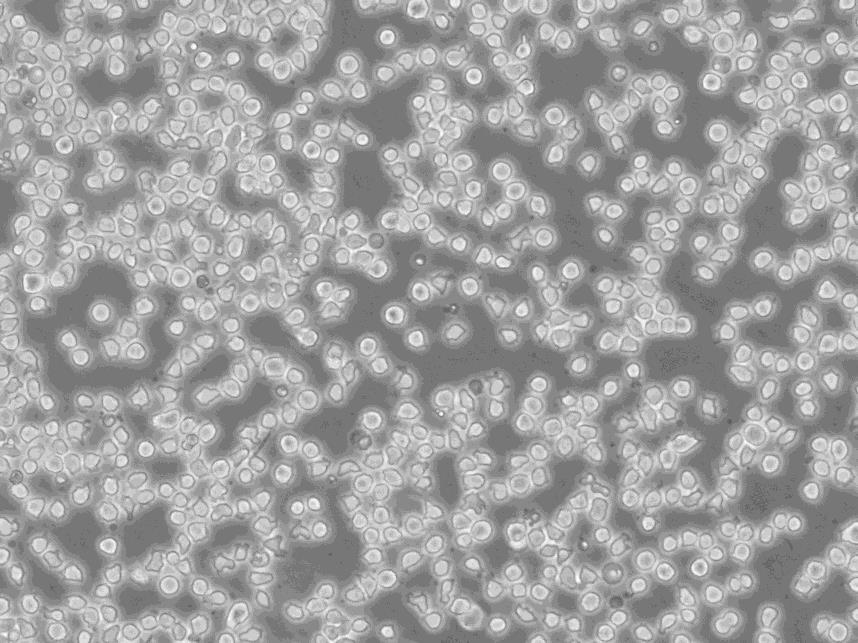

细胞形态:淋巴母细胞样

细胞生长:悬浮

细胞生长特性:悬浮生长